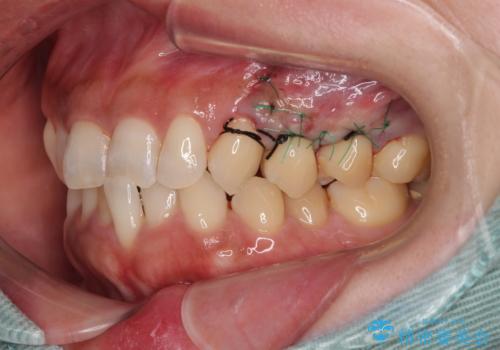

- 食いしばりと強いブラッシングにより、上顎小臼歯2本に知覚過敏を感じるようになったとのことで来院された患者様です。

歯肉退縮により歯根部が露出し、冷たい飲み物に痛みを感じる状態でした。

根面被覆を目的として歯肉移植術を行うこととしました。

歯肉が薄い状態であったため、歯肉退縮が起こりやすいと判断された患者様でした。

根面被覆を達成するとともに、歯肉の厚みを増すことで、今後歯肉退縮を起こしにくくするよう配慮した処置としました。